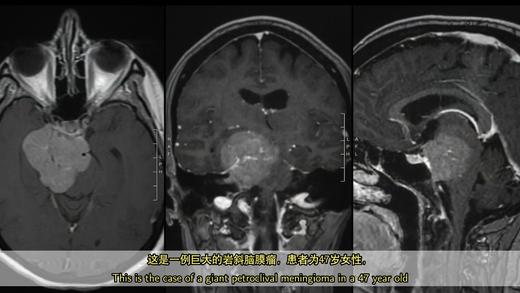

2021/Top3.巨大岩斜脑膜瘤手术(中英双语字幕)